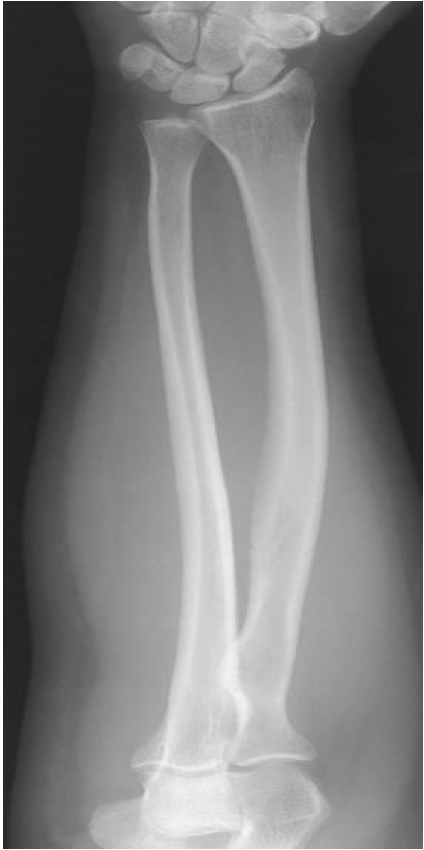

Evaluation Criteria for AP Forearm

• Carpals to distal humerus included

• Humeral epicondyles are in profile.

• Only slight, if any, superimposition of distal radioulnar joint

• Radial head, neck and tuberosity are slightly superimposed over the proximal ulna

• Open space b/w shafts of radius and ulna